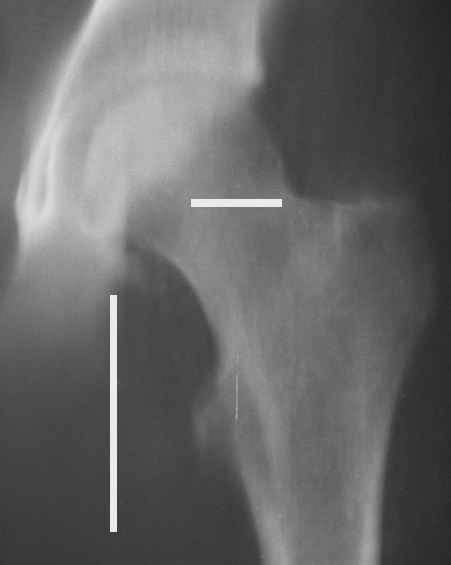

Уважаемые коллеги! Заканчивая обследование больного с переломо-вывихом бедра сделал ему обычные R-томограммы. Кажется удалось "поймать" и отломок и донорское место. Мои выводы - в скиаграмме. Считаю, что это передне-нижний фрагмент головки, образовавшийся вследствии отрывного перелома. На томограммах отломок обозначаю длинной стрелкой, а место откуда он оторвался - более короткой. Учитывая тот факт, что его размеры по КТ 25 х 15 мм считаю, что его фиксация на место необходима для профилактики артроза, что при 16-ти летнем возрасте пациента важно в плане максимального отодвигания эндопротезирования. Планирую оперировать его 24.05.05 г. Результаты представлю.

Прямой при поступлении

Несколько соображений к "картинкам". На прямом снимке и КТ-томограммах все типичные линии вертлужной впадины: крыша, передняя стенка, задняя стенка - сохранены. На КТ-сканах 6 и 7 появляется фрагментация головки. С учетом R-томограмм отломок расположен спереди-снизу, а не сзади-сверху от сустава, как написано в описании КТ.